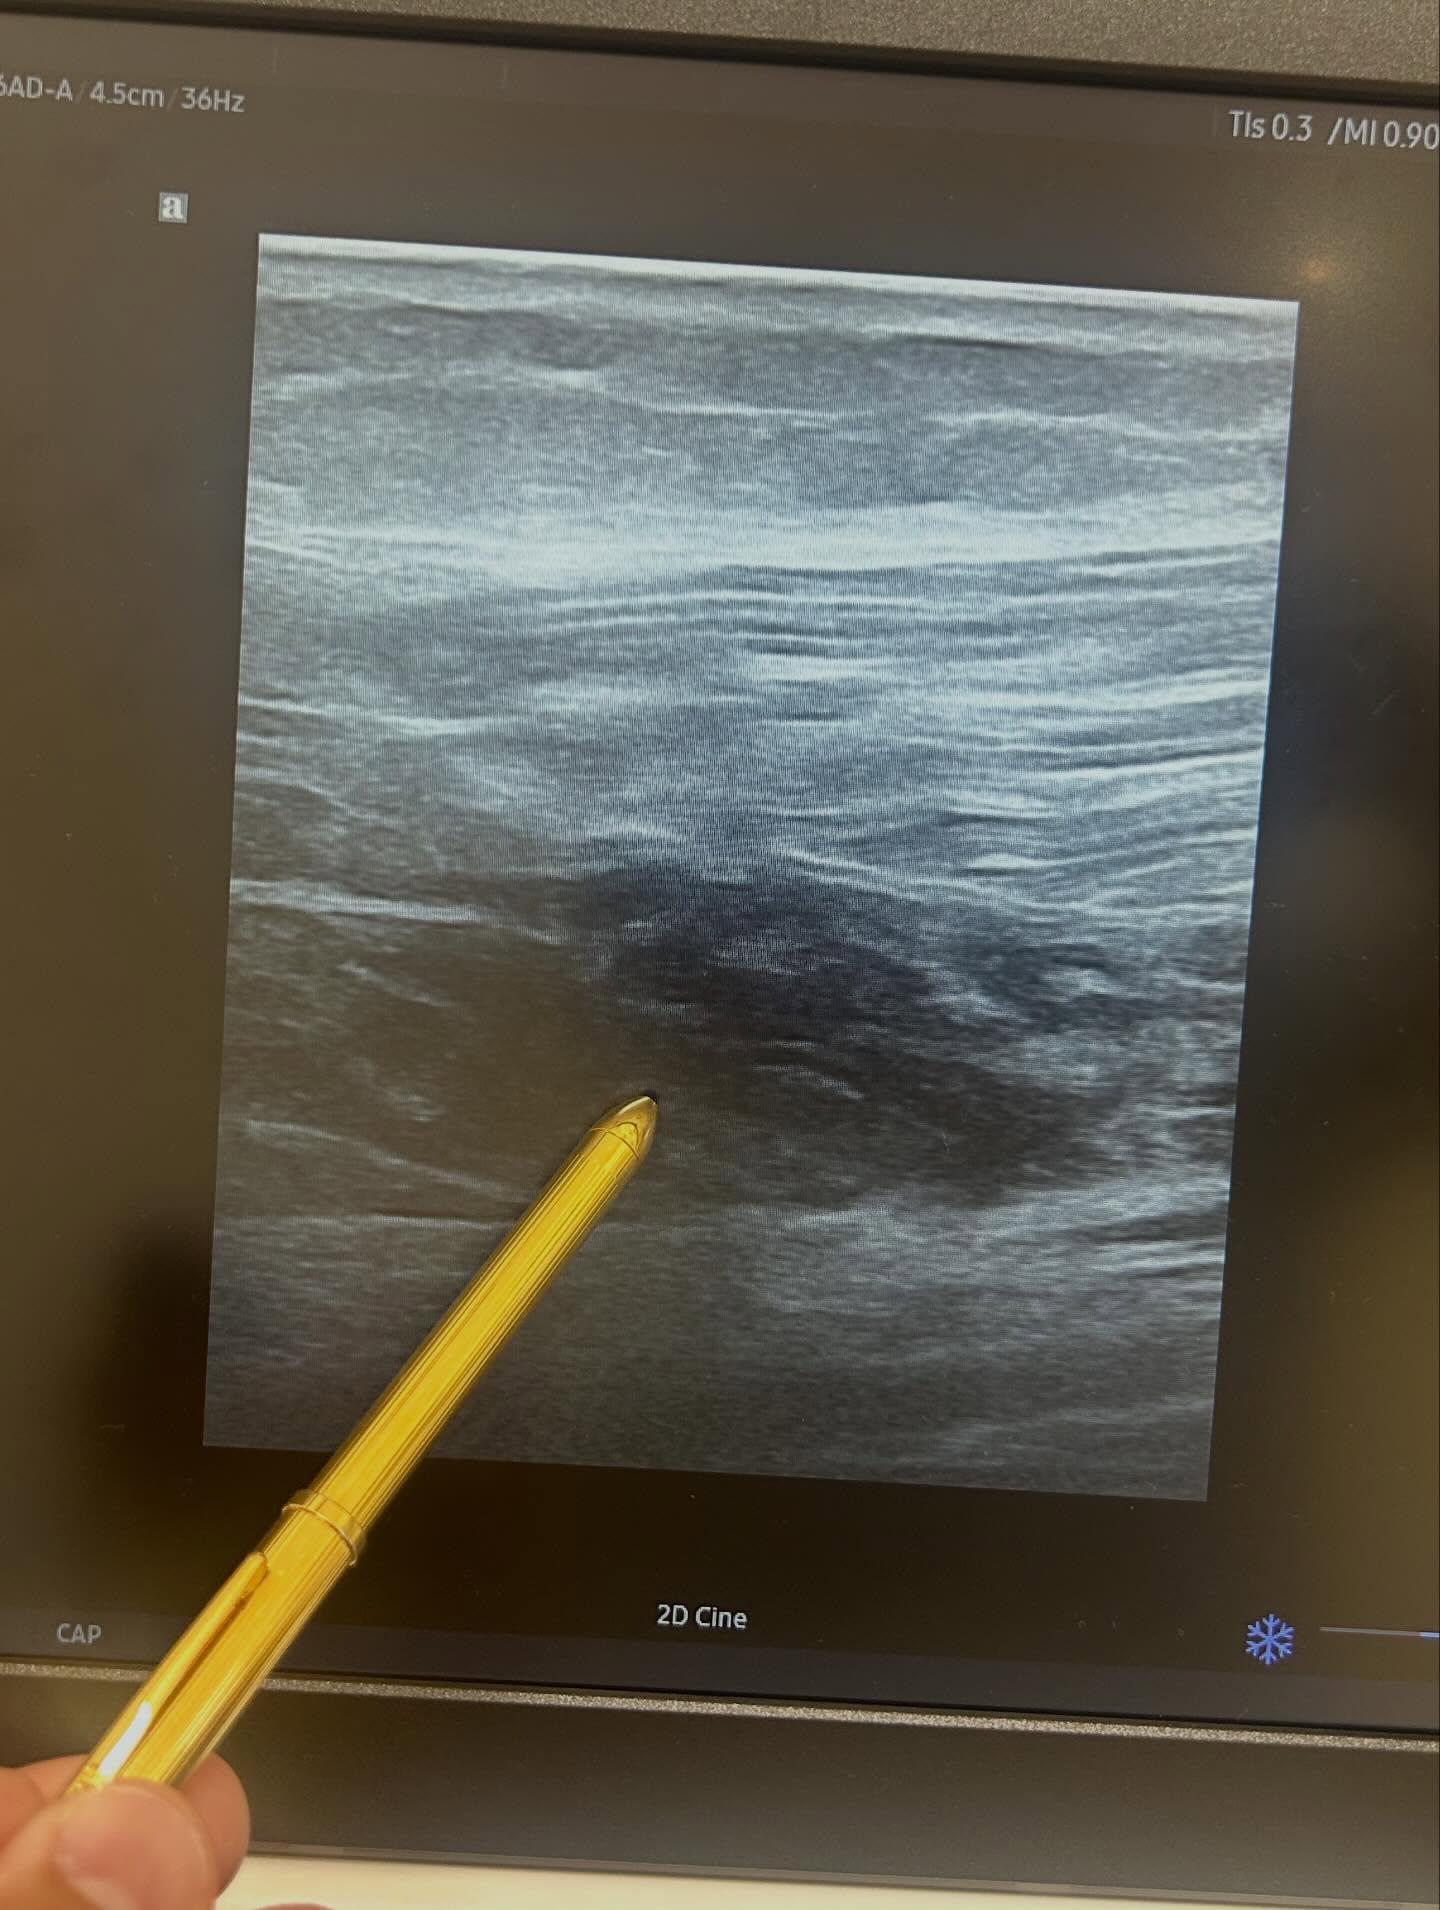

1週間前に少しダッシュをした際にブチっという音共に痛みを自覚し、

その後寛解がなく皮下出血が目立つ様になり、

友人からの紹介で本日受診された下関在住、40代男性の患者さん。

なかなかハードな肉離れでした![]()